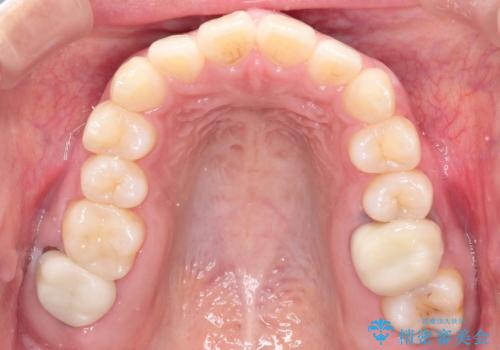

- 患者様は、奥歯(臼歯部)の反対咬合を主訴に来院されました。反対咬合は、噛み合わせのズレや顎の成長に影響を与える可能性があるため、早期の治療が重要です。診断の結果、上顎の幅が不足していることが原因と判明し、MARPE(骨固定式上顎急速拡大装置)を用いて上顎を広げる治療を計画しました。その後、歯列の調整のために審美ワイヤー矯正を行う方針としました。

MARPEを使用して上顎を拡大し、適切な歯列のスペースを確保しました。この拡大によって、反対咬合が改善され、正常な噛み合わせへと誘導できました。その後、目立ちにくいブラケットと白いワイヤーを使用した審美ワイヤー矯正を行い、歯列を整えました。治療が進むにつれ、噛み合わせのバランスが良くなり、見た目も自然な仕上がりに。